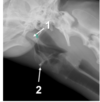

Which statement is false? (R318)

1 - for. intervertebrale

2 – proc. spinosus

3 – proc. articularis caudalis

3 – proc. articularis cranialis

1 - for. intervertebrale